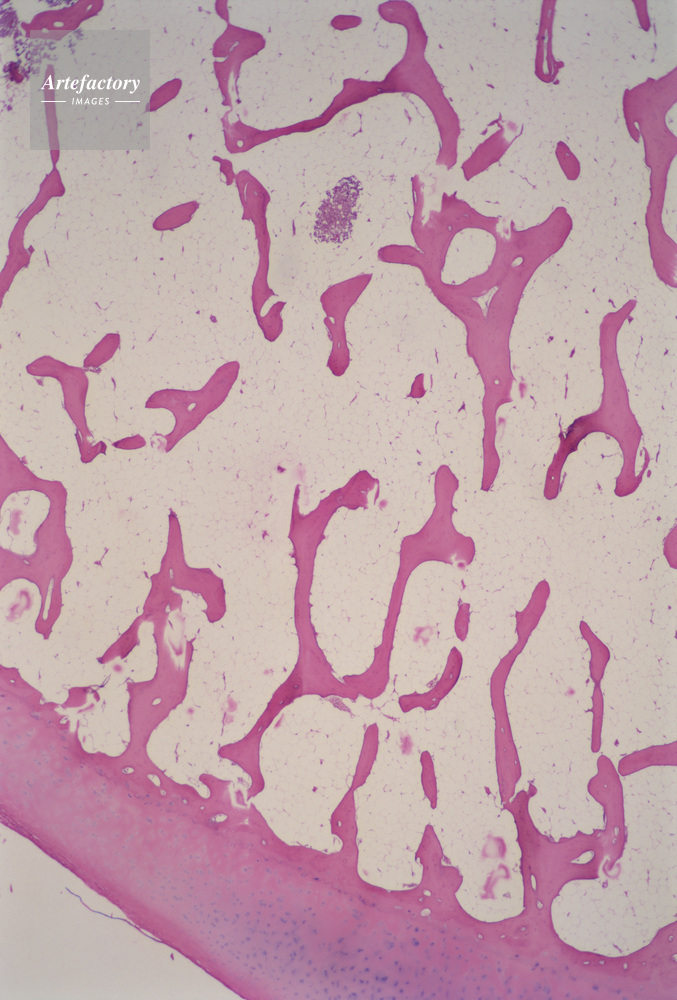

| キャプション | 海綿質骨,人間,10倍, | 制限事項 | ||

| ソース | ピクセル数 | 3767px × 5566px | ||

| 撮影地 | 印刷サイズ | 20.5cm × 30.4cm | ||